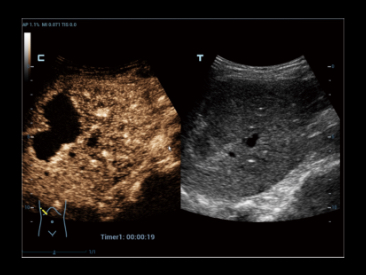

Przypadek kliniczny z wykorzystaniem technologii Glazing Flow (tryb power):

Unaczynienie nerki

Technologia Glazing Flow zapewnia wyra?n? wizualizacj? struktury t?tnicy ?ukowatej i t?tnicy mi?dzyp?atowej mniejszej z widokiem 3D.